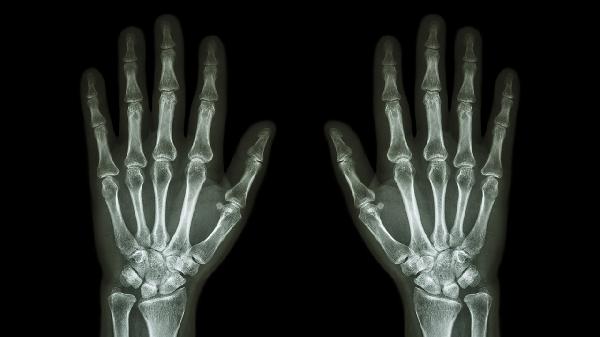

疑似骨折或韧带完全断裂需行X线或MRI检查确认。移位性骨折需手法复位后克氏针内固定,韧带断裂需手术缝合修复。术后需石膏固定4-6周,配合康复训练恢复关节功能。手术治疗适用于严重创伤导致的关节结构损伤。